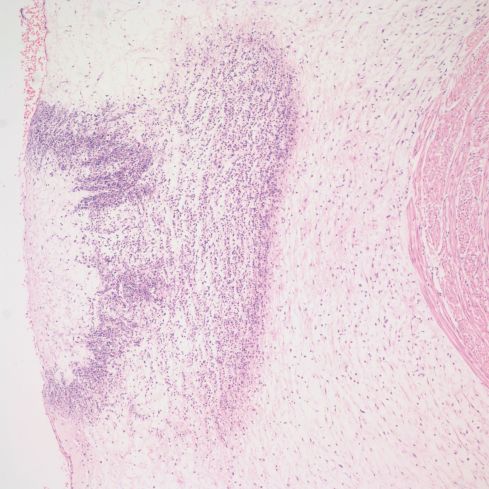

The unusual histologic picture is a clue to pathogenesis, and has often been likened to an ochterlany plate. In such a plate, antibody is in one well and antigen is in a distant well. Both antigen and antibody diffuse radially in media surrounding the wells. Where they meet in sufficient concentration, a crescent of precipitation occurs. In this analogy, the neutrophils “diffuse” from the vessel until they meet something diffusing from the umbilical surface. At this junction, there is a reaction that leads to a zone of necrosis analogous to the antibody-antigen precipitation in a ochterlany plate. This distinct geometric appearance is possible because there is no complex capillary bed anatomy. Why does “precipitation” occur in this situation, rather than free migration of neutrophils to the surface of the cord?. One plausible explanation is that the neutrophils are encountering their target, the organism. In the usual funisitis they are simply following a chemotactic stimulus to the amniotic fluid. However, if organisms are entering the cord, the ingestion of organisms or virally infected cells begins at the front between exiting neutrophils and entering organisms. Some of the organisms associated with necrotizing funisitis have been identified in the Wharton’s jelly including Treponema pallidum, Actinomyces meyeri, and unspecified bacteria. This theory cannot be directly proven since many cases to not demonstrate microorganisms with histological examination. However, some cases of SNF demonstrate neutrophils on the vascular side, the necrotizing zone in the middle, and numerous bacteria on the surface side of the umbilical cord (fig 8).

Fig 8a) Low power of an early/ mild, but typical. SNF lesion

Fig 8b) From the same cord, a higher power shows numerous short bacterial rods on the surface side of the band of necrosis.

Fig 8c) A different case, but with similar findings. These were both gram negative rods, but other cases had gram positive cocci.